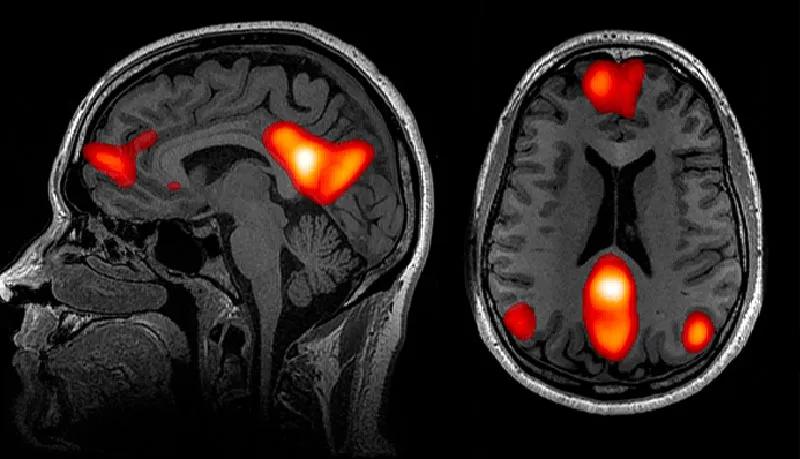

该研究2020年刊登于《自然-通讯》[21],其结果揭示了孤独感与当我们精神上处于待命状态时保持活跃的大脑默认网络(default network)密切相关。尽管研究表明默认网络中的活动消耗了大脑的大部分能量,“直到20年前我们都还不知道这一网络系统的存在。”比兹多克说。

比兹多克和他的团队发现长期孤独者的默认网络中某些区域的灰质体积不仅更大,而且他们的默认网络与大脑其他区域的连接也更紧密。此外,默认网络似乎参与了人类演化出的例如语言、预测未来和因果推理等独特能力的运用。更笼统地说,当我们想到他人时[22],包括当我们分析他们的意图时就会激活默认网络。

人脑的功能磁共振成像揭示了与默认网络相关的一些区域——当我们想到他人时最活跃的神经中枢区域。